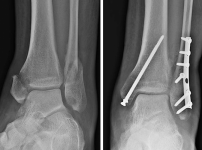

고덕 정형외과 발목골절 치료법 부터 재활까지, 부정유합 막는 골든타임 총정리

1. 발목골절, 단순히 뼈만 붙으면 끝일까요?발목골절은 단순히 뼈에 금이 간 것을 넘어, 관절의 안정성이 파열되는 중상인 경우가 많습니다. 특히 체중을 직접 지탱하는 부위이기 때문…